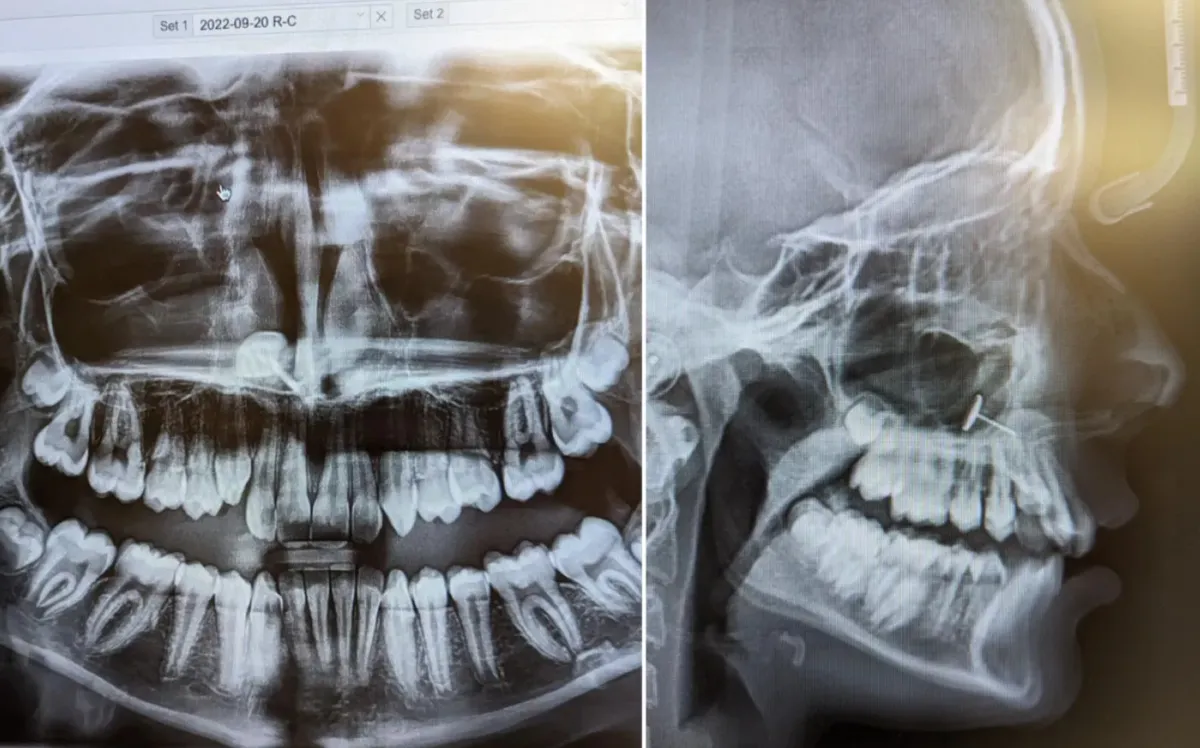

Hčer je peljala na rentgen zob. Ta je razkril nekaj, česar ne bi smelo biti tam |

Ko je Američanka 13-letno hčer peljala k ortodontu, da bi začeli postopek za zobni aparat, si ni predstavljala, kaj bo razkril rentgenski posnetek hče